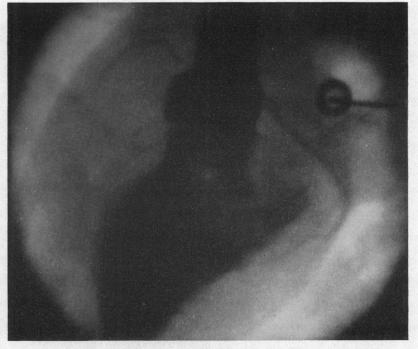

Cine-angiography of the coronary circulation in living dogs.

Br Heart J. 1960 Jan;22(1):54-60. doi: 10.1136/hrt.22.1.54.